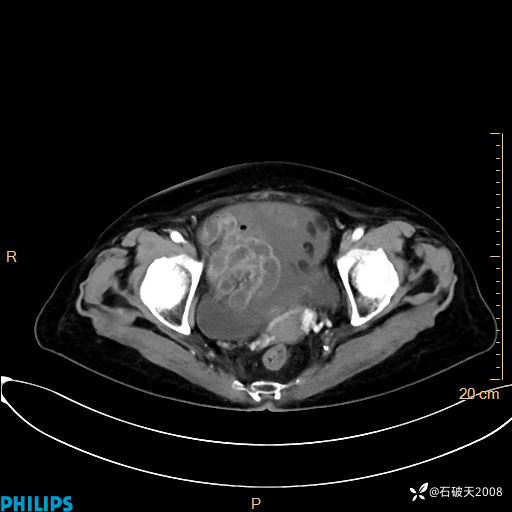

静脉期